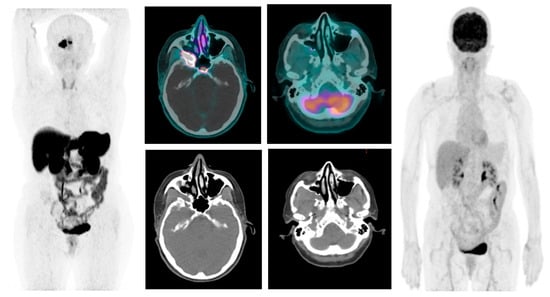

| Arrivi et al., 2023 (our case) | 77/F | Proptosis, loss of vision | PET-CT Ga-68 PET-CT 18-F, MRI, total body CT, CT Enterography Visual acuity exam | WD-NET G2 (Ki-67 6%) | WD-NET | Right Orbit | Lanreotide | OS 3 y |